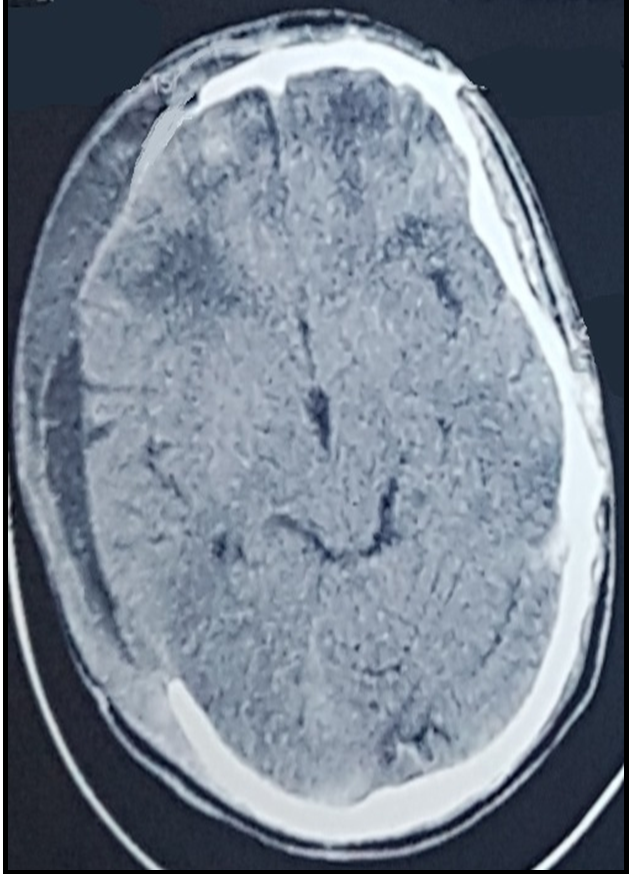

Post op ct scan showing adequate decompression.